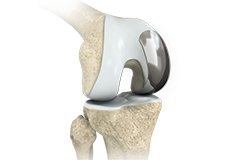

Knee Implants

Knee implants are artificial devices that form the essential parts of the knee during a knee replacement surgery. The knee implants vary by size, shape, and material. Implants are made of biocompatible materials that are accepted by the body without producing any rejection response.